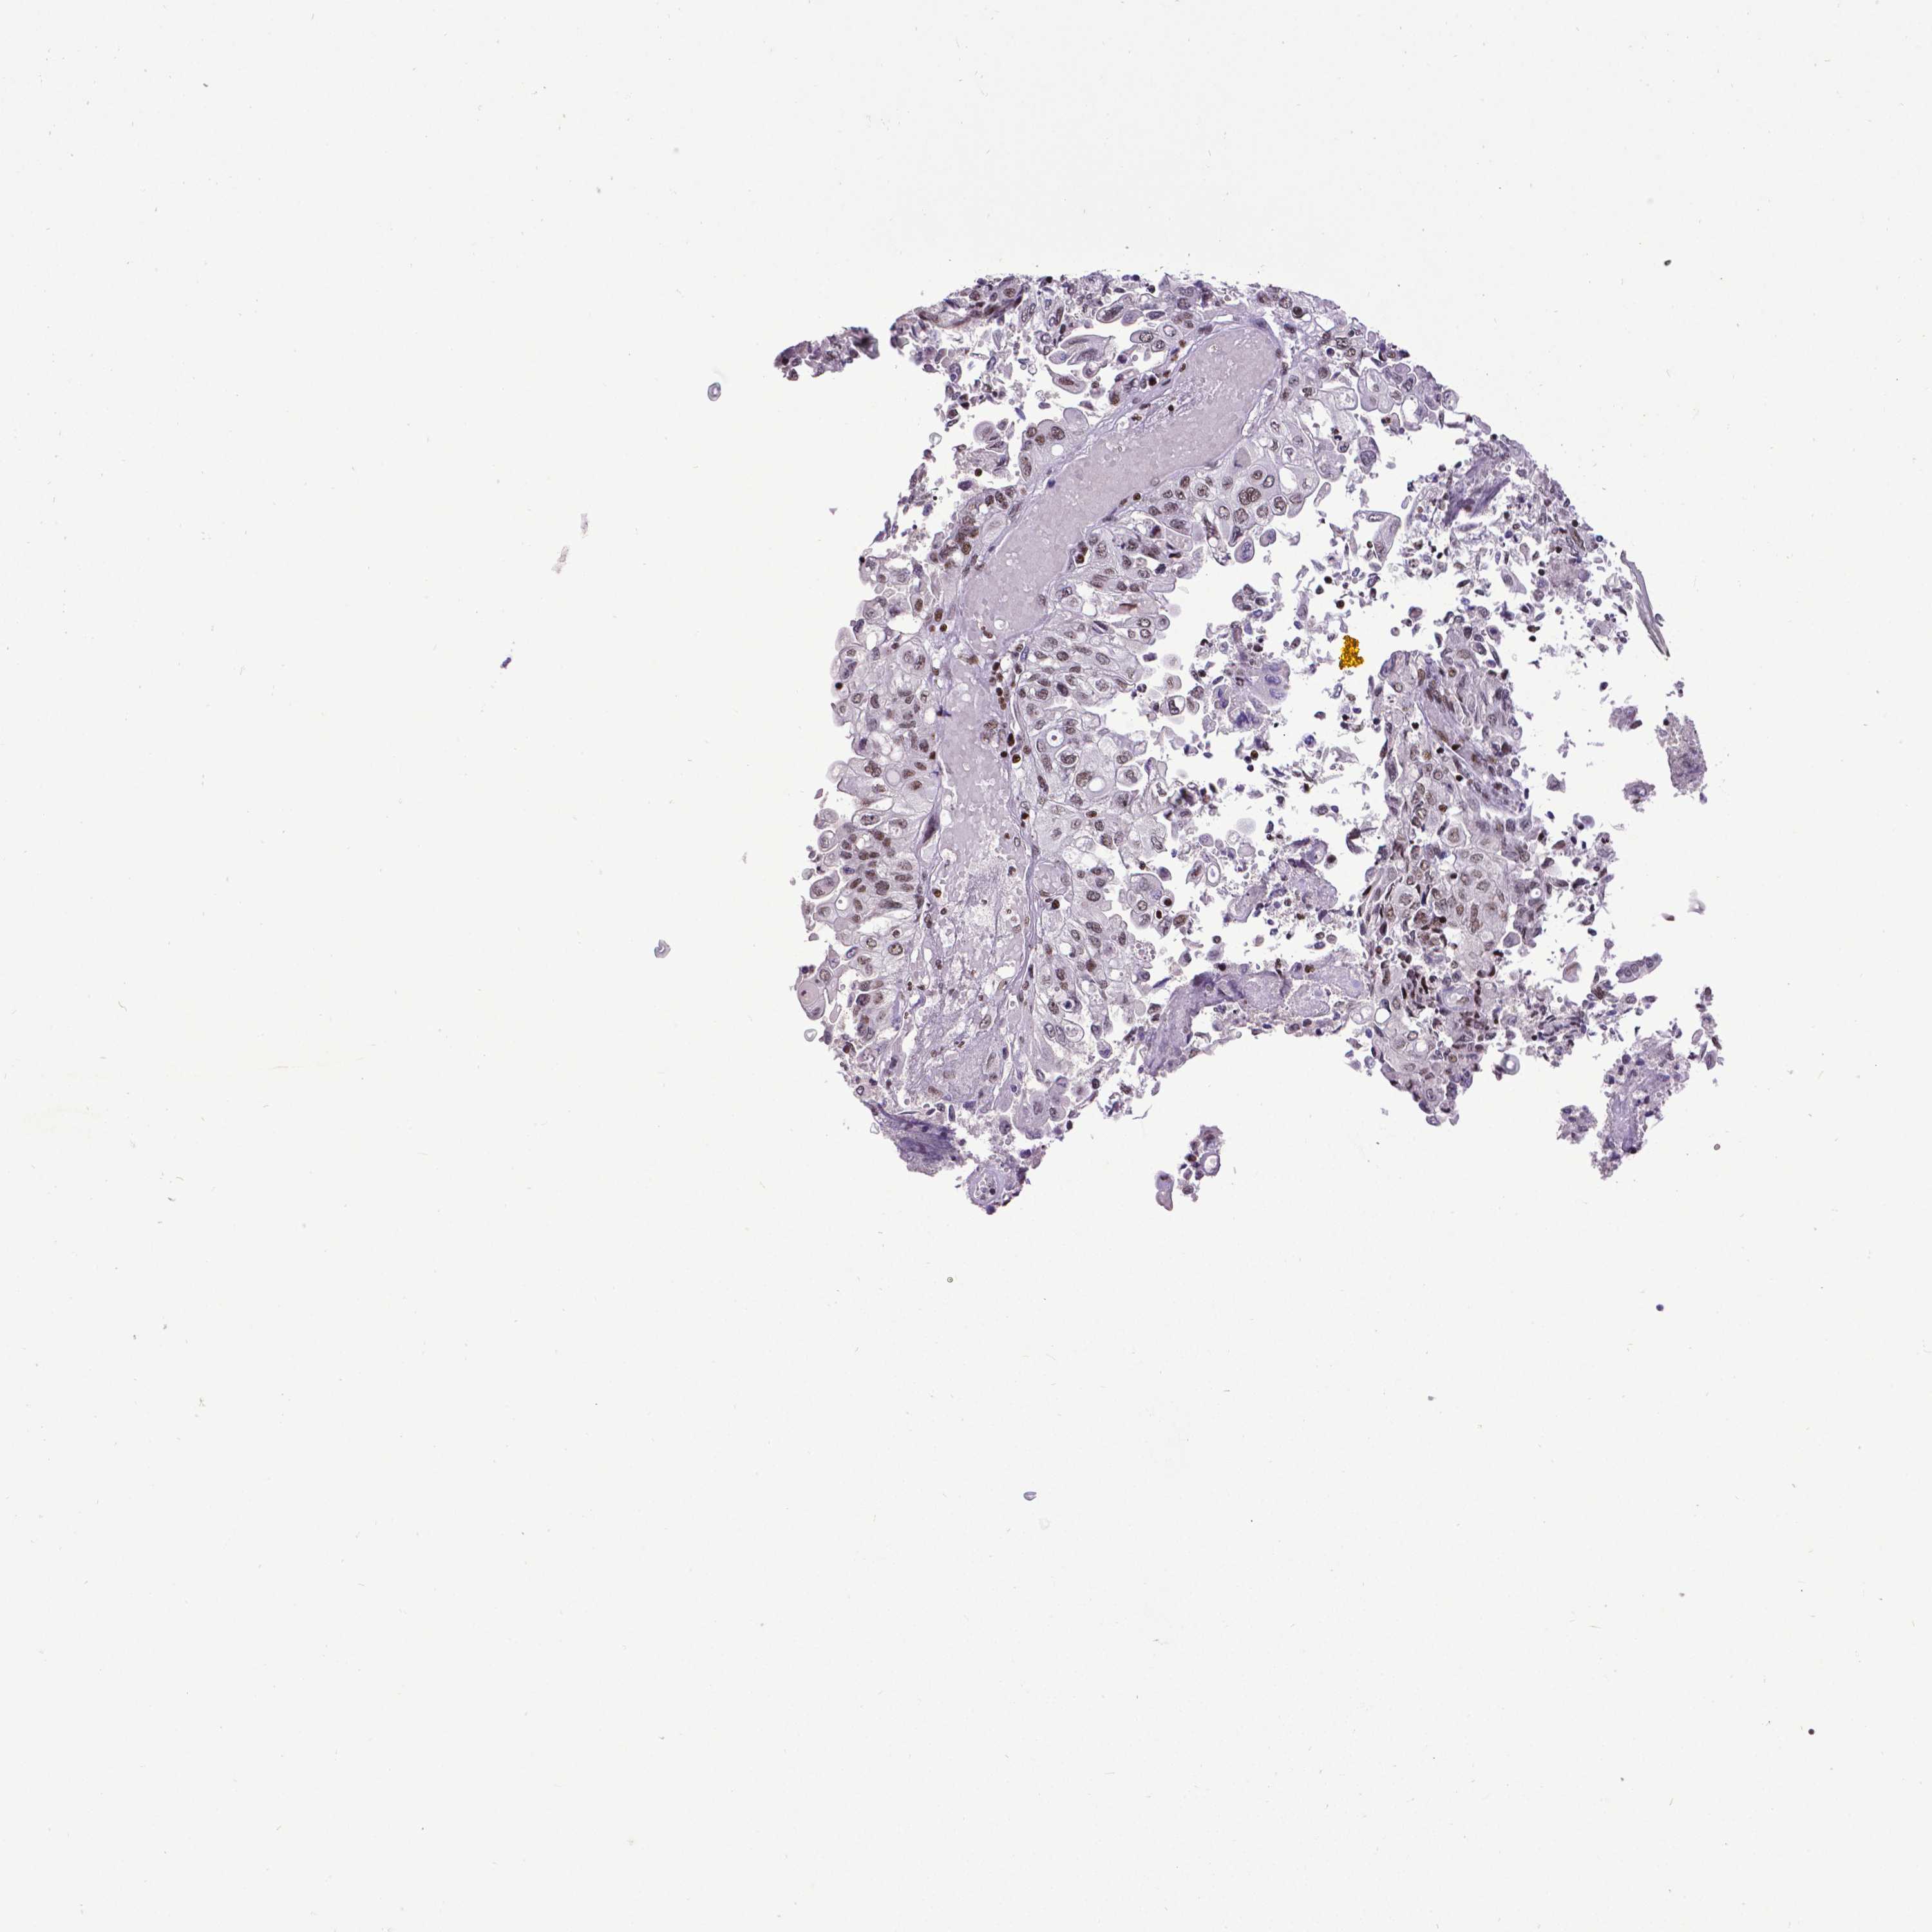

ENDOMETRIAL CANCER - Protein expressioni

A mouse-over function shows sample information and annotation data. Click on an image to view it in a full screen mode. Samples can be filtered based on level of antibody staining by selecting one or several of the following categories: high, medium, low and not detected. The assay and annotation is described here.

Note that samples used for immunohistochemistry by the Human Protein Atlas do not correspond to samples in the TCGA dataset.

Antibody stainingi

Antibody staining in the annotated cell types in the current human tissue is reported as not detected, low, medium, or high, based on conventional immunohistochemistry profiling in selected tissues. This score is based on the combination of the staining intensity and fraction of stained cells.

Each image is clickable and will lead to virtual microscopy that enables deeper exploration of all samples and also displays staining intensity scores, fraction scores and subcellular localization as well as patient and tissue information for each sample.

Antibody HPA004122

Antibody CAB062550

Antibody CAB068181

Antibody CAB068182